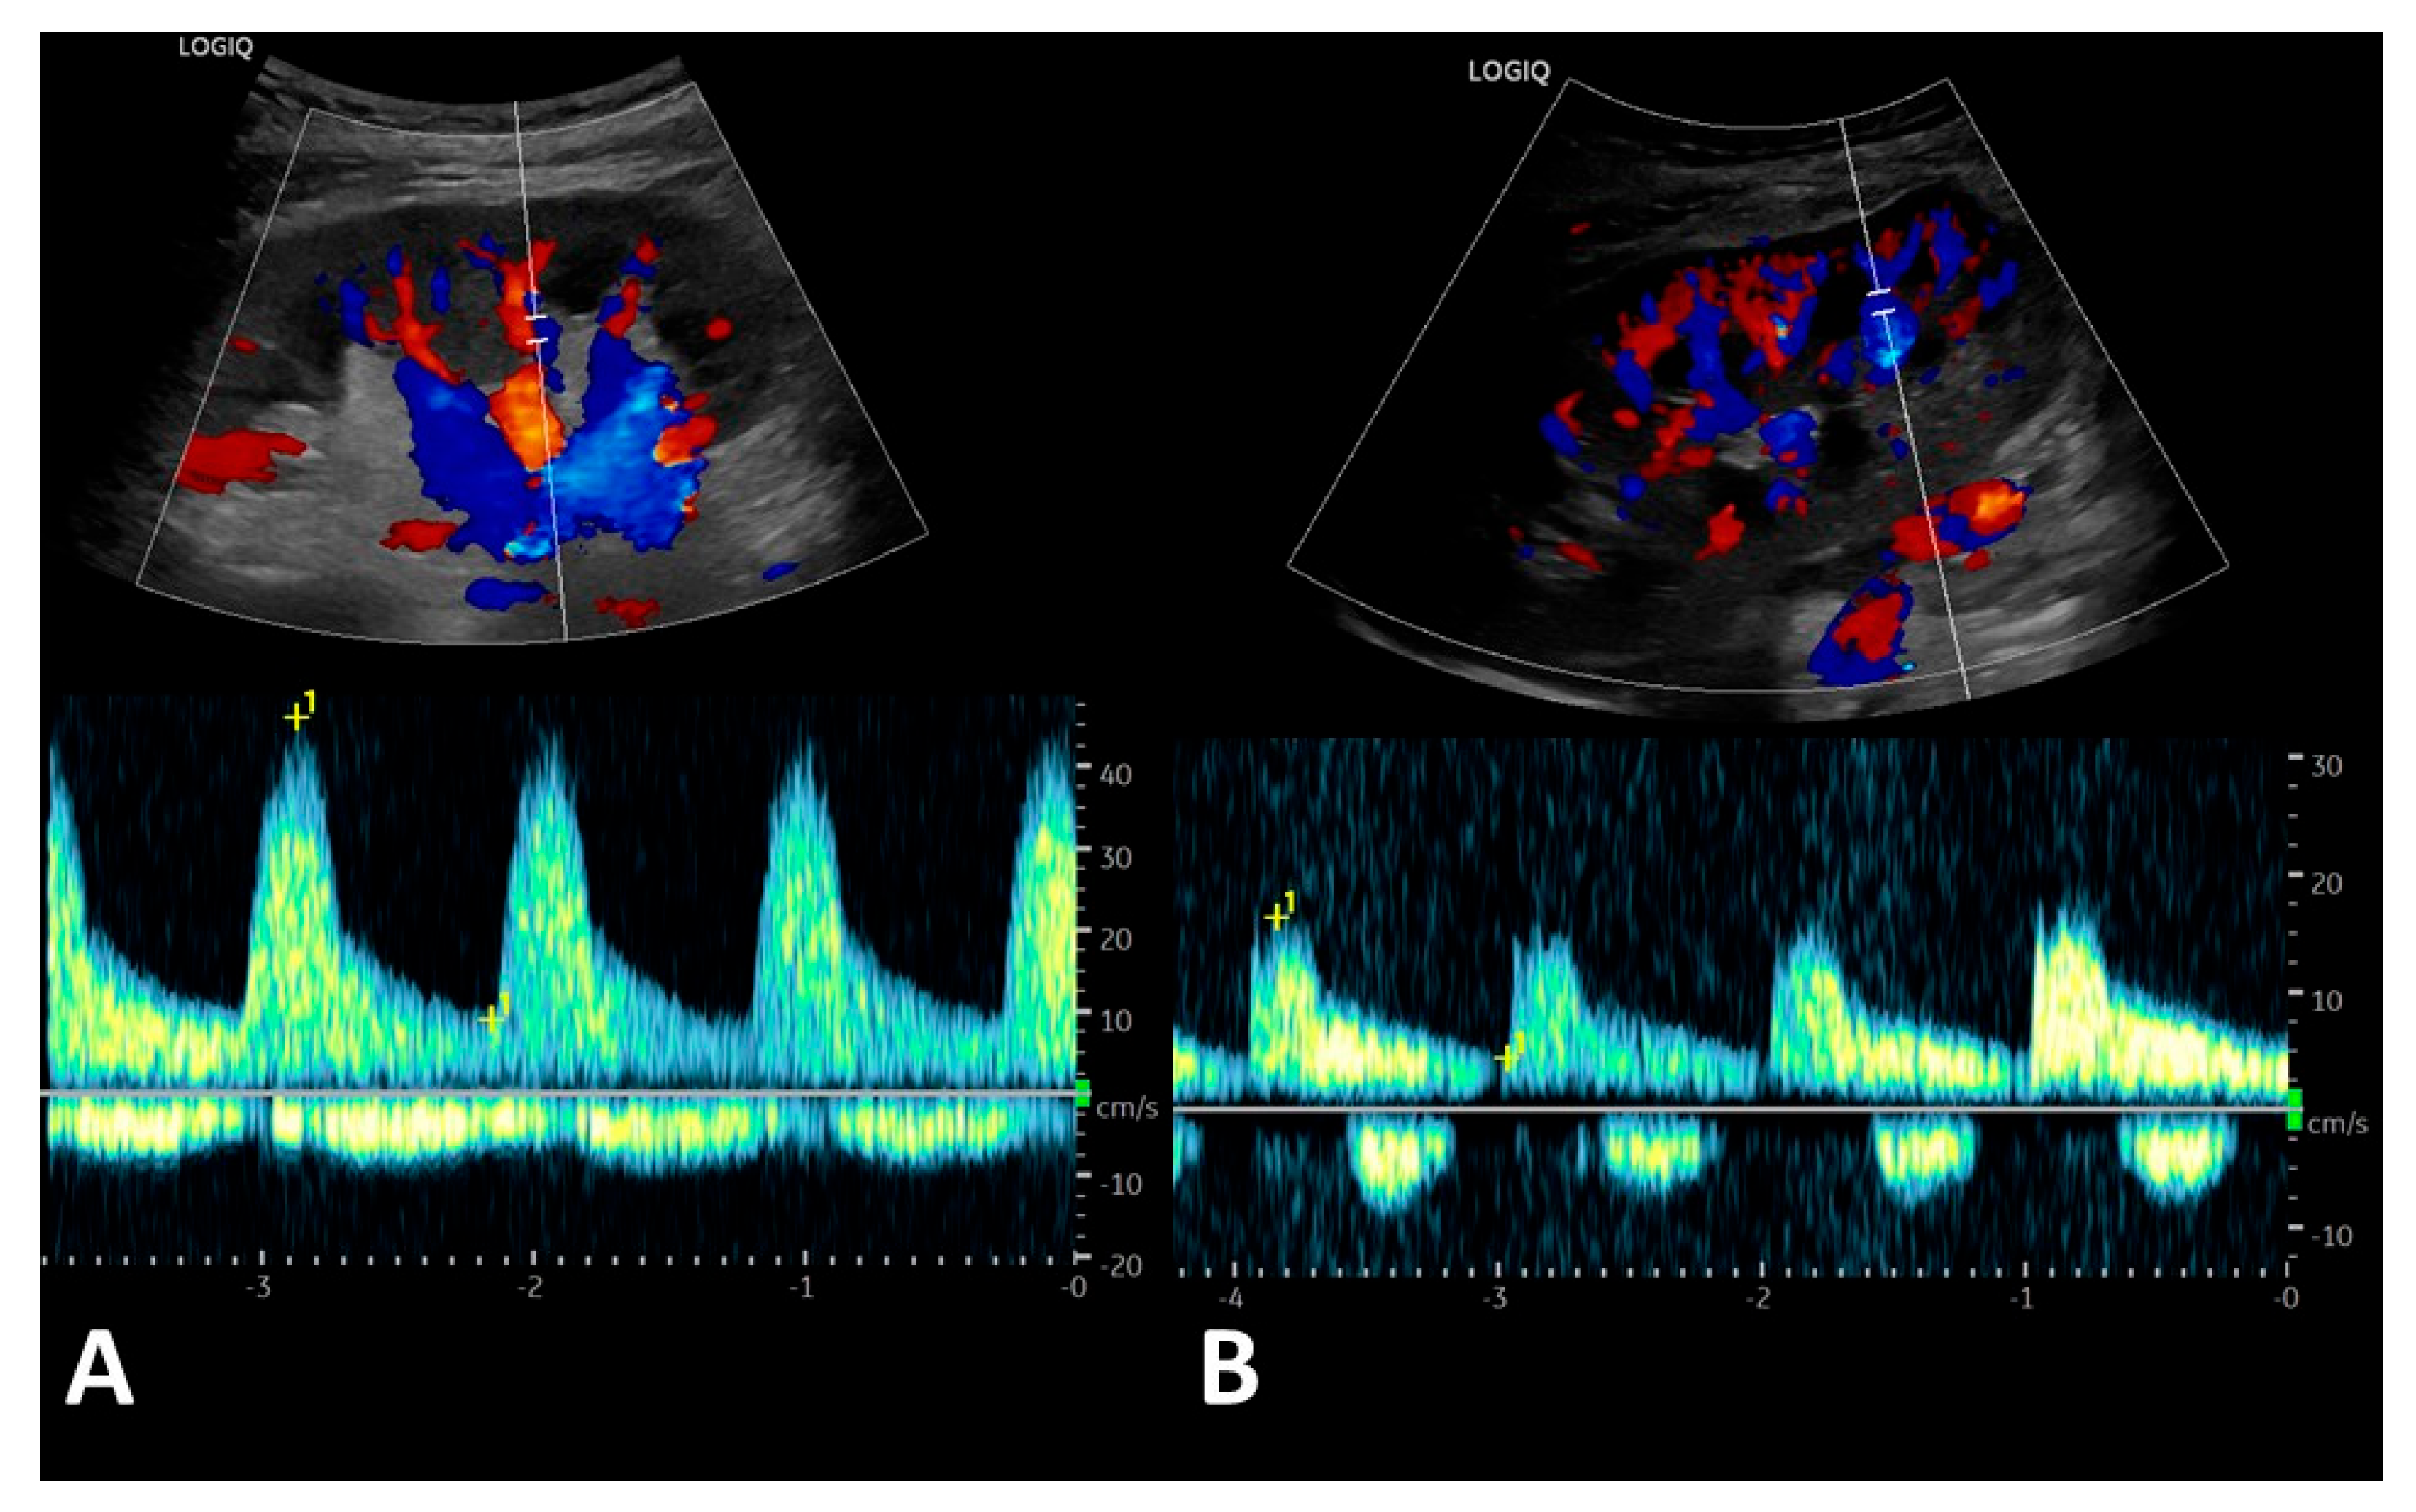

3.3. Post-Transplant Doppler Sonography Parameters of Transplanted Kidneys

| Renal vein profile | ||||

| 33 1 0 3 6 | 33 1 0 0 0 | 0 0 0 3 6 |